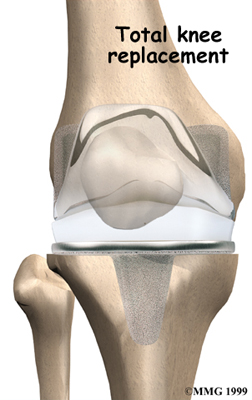

Artificial Knee Replacement

An artificial knee replacement is the ultimate solution for advanced knee OA.

Surgeons prefer not to put a new knee joint in patients younger than 60. This is because younger patients are generally more active and might put too much stress on the joint, causing it to loosen or even crack. A revision surgery to replace a damaged prosthesis is harder to do, has more possible complications, and is usually less successful than a first-time joint replacement surgery.

Related Document: FYZICAL North Richland Hills Guide to Artificial Joint Replacement of the Knee